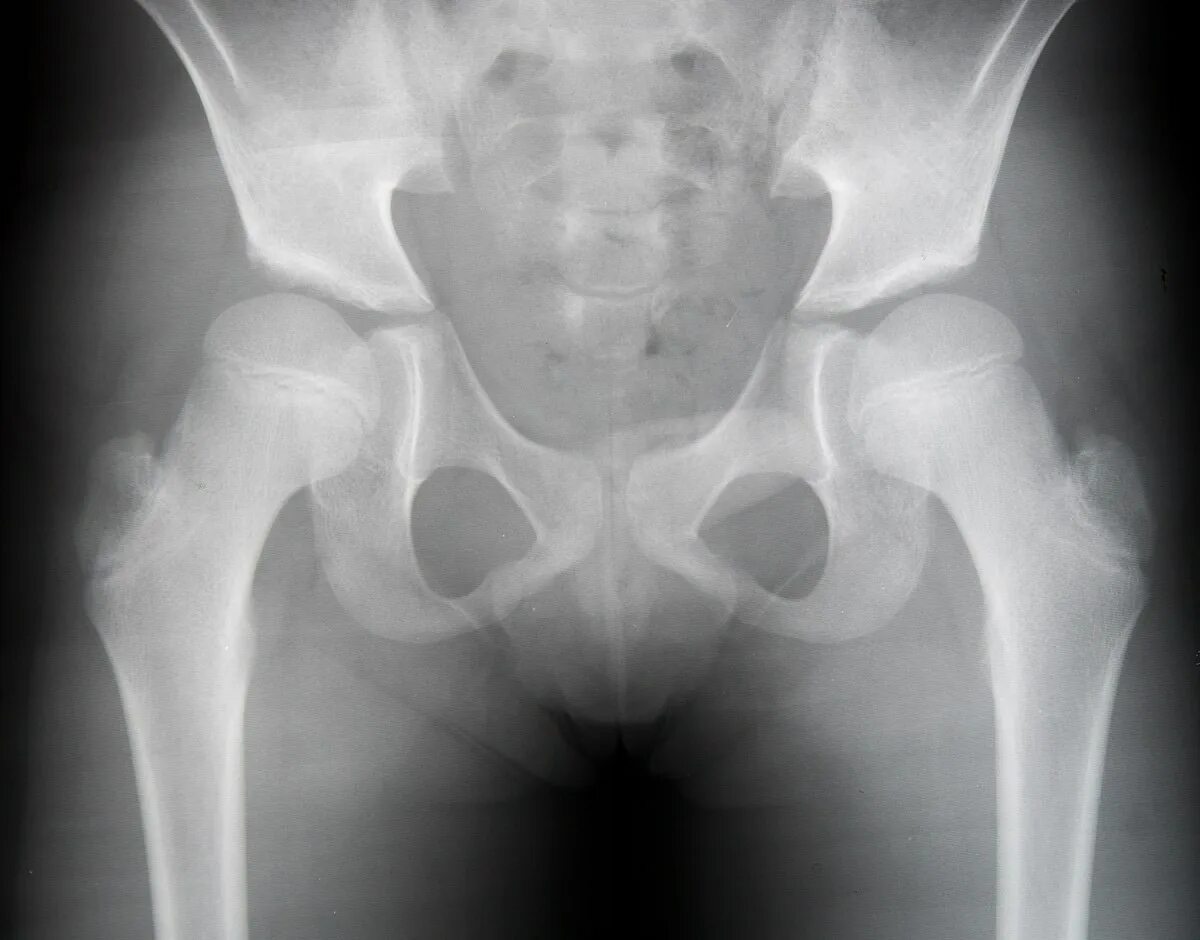

Дисплазия 7 лет